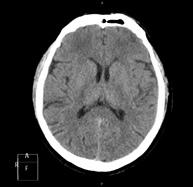

- Tórax- TC Tórax Prueba diagnóstica que consiste en obtener imágenes del tórax de alta definición anatómica (pulmones, corazón, mediastino, grandes vasos, caja torácica, etc.) mediante el empleo de un equipo de TC (Tomografía Computarizada). Dichas imágenes se estudian posteriormente en una estación de trabajo que permite reconstrucciones bidimendionales en diferentes planos del espacio y también reconstrucciones 3D (volumétricas). Algunos estudios requieren el empleo de contraste yodado para mejorar la definición de las imágenes. Prueba diagnóstica que consiste en obtener imágenes del tórax de alta definición anatómica (pulmones, corazón, mediastino, grandes vasos, caja torácica, etc.) mediante el empleo de un equipo de TC (Tomografía Computarizada). Dichas imágenes se estudian posteriormente en una estación de trabajo que permite reconstrucciones bidimendionales en diferentes planos del espacio y también reconstrucciones 3D (volumétricas). Algunos estudios requieren el empleo de contraste yodado para mejorar la definición de las imágenes.